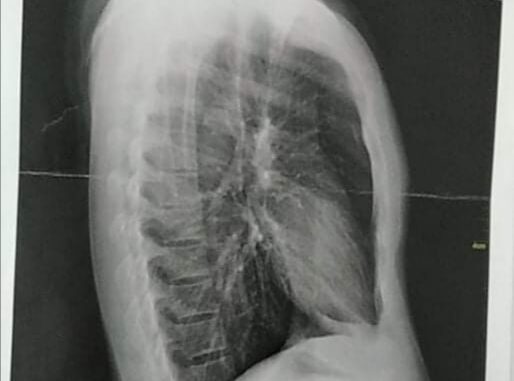

Zaprt sem v Centru za tujce v Postojni. Tukaj sem bil že večkrat tepen. Prvi incident se je zgodil enkrat oktobra malo po 12h. Poskušal sem izkoristiti čas, v katerem imamo na voljo uporabo interneta, da sem po telefonu govoril s svojo ženo. Ob 12h je k meni pristopila socialna delavka in zahtevala, naj pogovor prekinem. Rekel sem ji, da je nujna zadeva in prosil za še 2 minuti. Odšla je v spodnje nadstropje in kmalu so od tam prišli štirje policisti. Glave so imeli pokrite z maskami, da se jim ni videlo obrazov, le oči. Odpeljali so me v mojo sobo in me začeli tepsti. Eden me je zelo močno sunil v prsa, drug v rebra. Na obeh mestih imam še vedno močne bolečine, en zob pa je zlomljen. Mislim, da imam tudi zlomljena rebra. Po tem so me odvlekli v samico, kjer sem bi zaprt tri dni.

Na hitro me je pregledal zdravnik iz Centra za tujce, ki je zgolj povedal, da ni hujših poškodb. Vendar to ne drži, še vedno imam hude bolečine v prsih in rebrih, težave imam tudi z dihanjem, kot bi imel astmo. Zelo sem vznemirjen in prestrašen, zdaj pa mi kot nalašč ves čas grozijo s samico. Grozijo mi tudi, da me bodo odpeljali na Hrvaško in da bom tam “že videl, kaj mi bodo naredili policaji”.

Brez tabletov zaradi bolečin pa sploh ne morem zaspati.